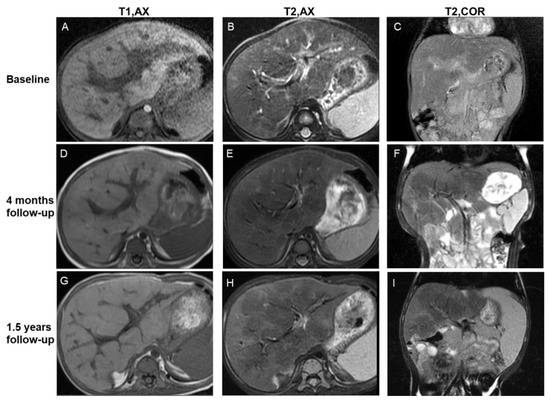

- Evolution of parenchymal lesions in eight patients with multiple MRI scans

- Evolution of periportal lesions in eight patients with multiple MRI scans

4.2. Evolution of Lesions